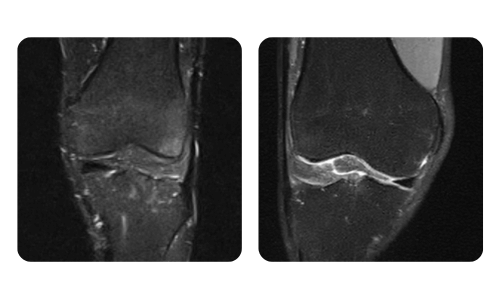

I progressi dei nostri pazienti, misurati prima e dopo la terapia iperbarica, riflettono l'efficacia e l'impatto positivo del trattamento. Scopri i risultati documentati della terapia iperbarica presso la clinica Hyperbarium Oradea, basati su valutazioni cliniche e dati oggettivi che evidenziano miglioramenti significativi in diverse condizioni.